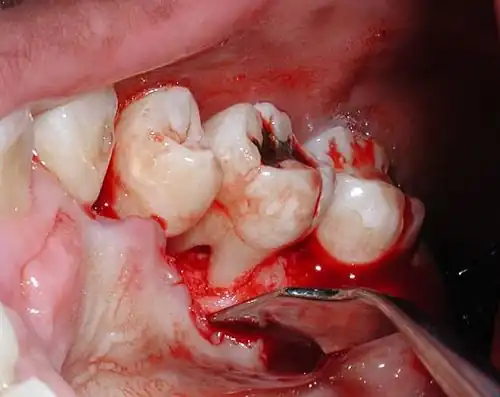

Furcation defect

In dentistry, a furcation defect is bone loss, usually a result of periodontal disease, affecting the base of the root trunk of a tooth where two or more roots meet (bifurcation or trifurcation). The extent and configuration of the defect are factors in both diagnosis and treatment planning.[1]

Diagnosis

Nabers probe is used to check for furcation involvement clinically. Recently, cone beam computerised technology (CBCT) has also be used to detect furcation.[5] Periapical and interproximal intraoral radiographs can help diagnosing and locating the furcation.

Only multirooted teeth have furcation. Therefore, upper first premolar, maxillary and mandibular molars may be involved. Upper premolars have one buccal and one palatal root. Maxillary molars have three roots, a mesio-buccal root, disto-buccal root and a palatal root. Mandibular molars have one mesial and one distal root, and so.